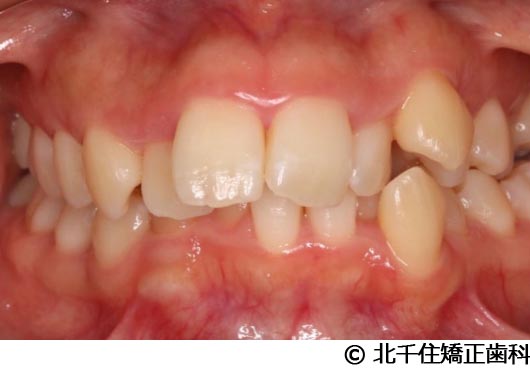

【症例3】叢生

- 治療前

- 治療後

- 治療名

- 叢生

- 費用

- 1,125,000円(税込)

- 期間

- 2年1ヵ月

- 治療回数

- 26回

- 通院頻度

- 1ヵ月ごと

- 年齢・性別

- 19歳3ヵ月・女性(初診時)

主訴:デコボコ、口元の突出

上下顎第一小臼歯4本を抜歯してワイヤー矯正(セラミックブラケット)。

叢生に対し抜歯を併用した矯正治療により、歯列および咬合関係の調整を行った症例である。治療後は保定装置を使用し、歯列および咬合の安定維持を目的として定期的な経過観察を行っている。

※治療結果は個人差があります。

治療を行う上での注意点(リスク・副作用)

歯磨き不良に伴うカリエスや歯周病、歯根吸収など。